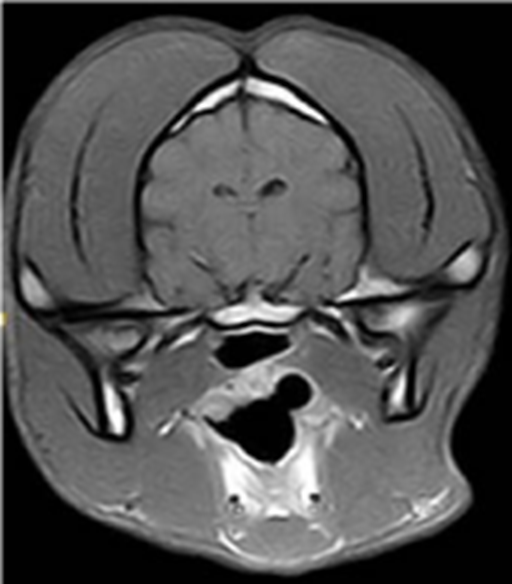

MRI is a well-suited tool for in vivo cell tracking because of its high spatial resolution. It is due to the fact that hydrogen protons will align and process through which these protons coming back to their initial state is known as the relaxation phenomenon. Two independent processes, longitude relaxation (T1 recovery) and transverse relaxation (T2 decay) are monitored to generate the MR image. Paramagnetic and super paramagnetic contrast agents change the relaxation time significantly by transferring their magnetic relaxation to the surrounding nuclei, so by selecting a specific monitoring delay the signal between contrasted and non-contrasted areas becomes significant (Figure 5). In recent years, the use of SPIONs to visualize cell migration has been used clinically, showing the potential capabilities of monitoring cellular therapies with MRI. The detection threshold for SPION-labelled cells is influenced by acquisition parameters and magnetic field strength. The drawback of MRI is that it requires high concentrations of contrast agents because it has low sensitivity. A high concentration of iron oxide increases toxicity and causes concern. However, making aggregated particles is an alternative way to increase the sensitivity. Aggregated particles have a stronger magnetic field, therefore increasing the concentration is not necessary.53 In line with the recent studies on cellular fate and toxicity of polymer coated iron oxides, most of the iron oxide nanoparticulate which were used clinically as contrast agents has been removed from use in humans in the UK. These include Feridex IV® and Luminex®. As such research is now underway to use highly rigid coatings which produce biocompatible nanoparticulate which maintain the unique contrast ability of their predecessors.

Figure 5 Typical MR image of a healthy canine brain using T2 imaging agent showing difference in contrast between various areas.